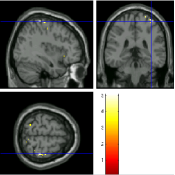

Once the reduced FOV images are available, the proposed pMRI 4D-UWR-SENSE algorithm and its early UWR-SENSE version have been utilized in a final step to reconstruct the full FOV EPI images and compared to the mSENSE Siemens solution. For the wavelet-based regularization, dyadic Symmlet orthonormal wavelet bases [48] associated with filters of length 8 have been used over resolution levels. The reconstructed EPI images then enter in our fMRI study in order to measure the impact of the reconstruction method choice on brain activity detection. Note also that the proposed reconstruction algorithm requires the estimation of the coil sensitivity maps (matrix in Eq. (2)). As proposed in [4], the latter were estimated by dividing the coil-specific images by the module of the Sum Of Squares (SOS) images, which are computed from the specific acquisition of the -space centre (24 lines) before the scans. The same sensitivity map estimation is then used for all the compared methods. Fig. 5 compares the two pMRI reconstruction algorithms to illustrate on axial, coronal and sagittal EPI slices how the mSENSE reconstruction artifacts have been removed using the 4D-UWR-SENSE approach. Reconstructed mSENSE images actually present large artifacts located both at the centre and boundaries of the brain in sensory and cognitive regions (temporal lobes, frontal and motor cortices, …). This results in SNR loss and thus may have a dramatic impact for activation detection in these brain regions. Note that these conclusions are reproducible across subjects although the artifacts may appear on different slices (see red circles in Fig. 5). One can also notice that some residual artifacts still exist in the reconstructed images with our pipeline especially for . Such strong artifacts are only attenuated and not fully removed because of the high level of information loss at .

| mSENSE | 4D-UWR-SENSE | ||

| Axial |  |

|

|

| Coronal | |||

| Sagittal | |||

| Axial |  |

|

|

| Coronal | |||

| Sagittal |